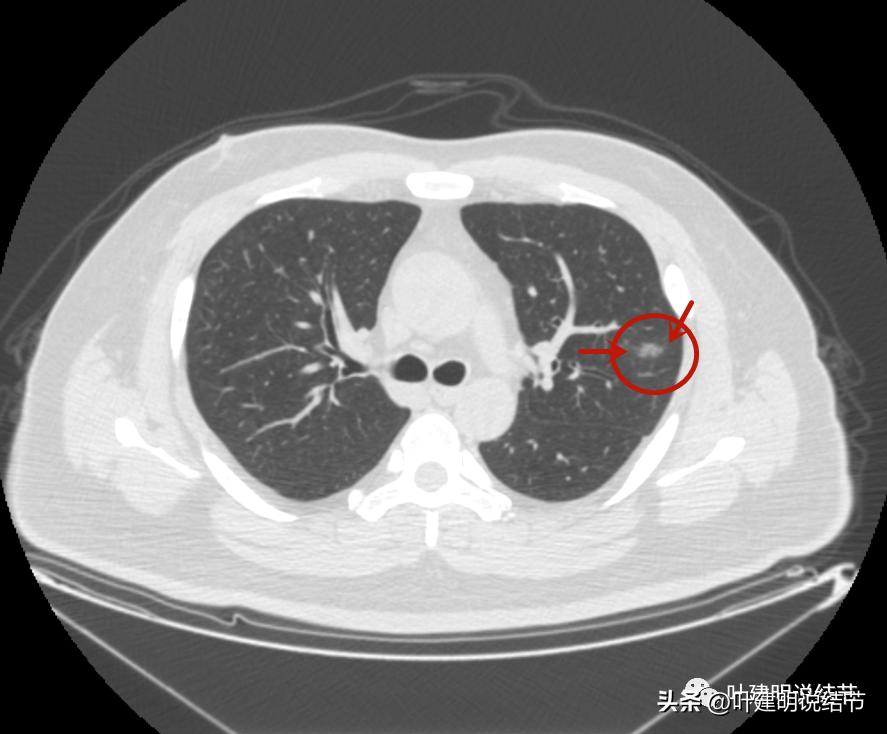

右上叶倒又出现了新的病灶:

右上病灶1:是新出现的,密度甚低,但轮廓较清,不典型增生吗?

右上病灶2:新出现的,整体轮廓较清,但感觉较散在,不致密,也不是圆形或类圆形,大概是炎性的吧!

2020年时同样位置是没有异常的: